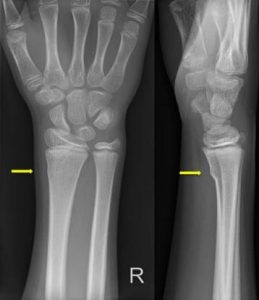

Uw kind heeft een kleine breuk in de ellepijp of het spaakbeen ter hoogte van de pols (torus fractuur). Het is een knikje in het bot. We behandelen het met een brace en een sling. Dit is een soort mitella.

- Uw kind heeft een kleine breuk in de ellepijp of het spaakbeen ter hoogte van de pols.